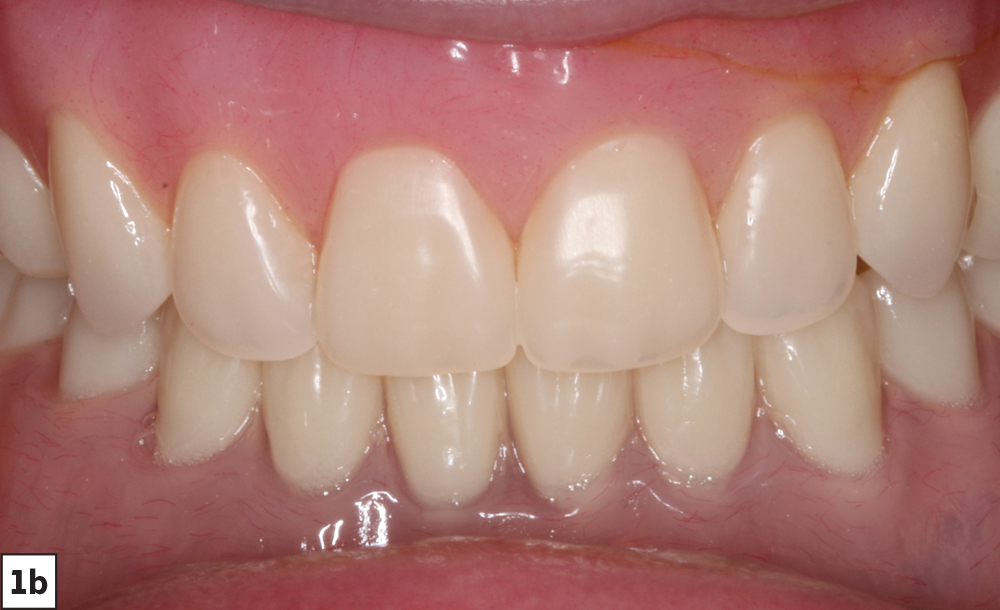

Our patient is a middle-aged female who presented with a chief complaint of ill-fitting, unstable maxillary and mandibular conventional dentures. We discussed several options, including relining her existing dentures, fabrication of new conventional dentures, implant-retained overdentures and fixed implant-supported prostheses. The patient opted for implant placement and restoration with a Locator Overdenture — which would provide an effective, economical means of addressing the patient’s needs and improving prosthetic stability and dental function.